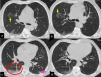

Case 3: 52 year old female. Bilateral central and peripheral ground glass attenuation and vessel enlargement. In the right upper lobe and in the left lower lobe the consolidative aspect present in supine position reduced significantly in the prone. Moreover, veins decreased in caliber (Fig.2).

CT scan in supine (a, c, e, g) and prone (b, d, f, h) position. Bilateral peripheral ground glass attenuation, with solid component in the right postero-basal segment (red ellipse) and left postero-basal segment of the left lower lobe (yellow ellipse). The density of the attenuation decreases significantly with prone positioning.

Vessel enlargement, consisting in venous dilatation, is present in both lower lobes, with a significant reduction in caliber with prone positioning (in the left lower lobe: 3 mm vs 5,4 mm).